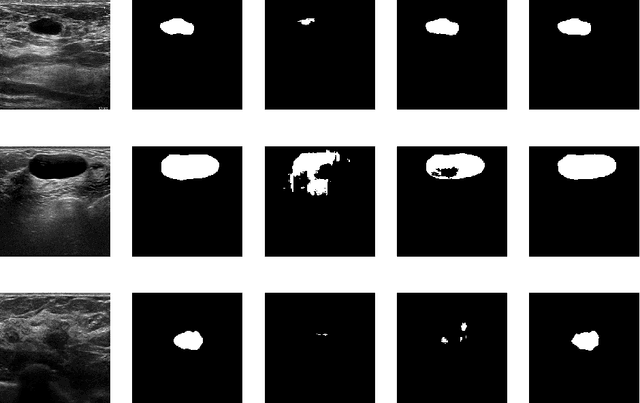

Fine-tuning a network which has been trained on a large dataset is an alternative to full training in order to overcome the problem of scarce and expensive data in medical applications. While the shallow layers of the network are usually kept unchanged, deeper layers are modified according to the new dataset. This approach may not work for ultrasound images due to their drastically different appearance. In this study, we investigated the effect of fine-tuning different layers of a U-Net which was trained on segmentation of natural images in breast ultrasound image segmentation. Tuning the contracting part and fixing the expanding part resulted in substantially better results compared to fixing the contracting part and tuning the expanding part. Furthermore, we showed that starting to fine-tune the U-Net from the shallow layers and gradually including more layers will lead to a better performance compared to fine-tuning the network from the deep layers moving back to shallow layers. We did not observe the same results on segmentation of X-ray images, which have different salient features compared to ultrasound, it may therefore be more appropriate to fine-tune the shallow layers rather than deep layers. Shallow layers learn lower level features (including speckle pattern, and probably the noise and artifact properties) which are critical in automatic segmentation in this modality.